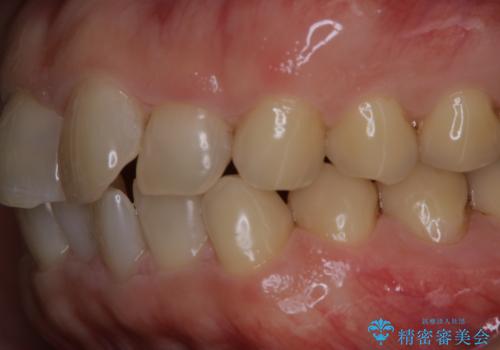

細かいステインをPMTCでOFF

- 歯ブラシをしてもとれないステインが気になるとのことで来院されました。PMTC60分コースを行いました。

PMTCは、歯に付着した汚れを除去していくため、着色が気になる場合にも行うことができます。ご自身でのセルフケアだけで着色を落とそうとすると、逆に歯を傷つけてしまったり、精密に汚れを除去できないこともあります。また、日常生活で着色しやすい飲食物を避けたりすることはストレスに感じてしまったり、あまり現実的ではありません。

毎日丁寧に歯磨きをしていても、日常生活での飲食物などにより着色してしまうことはあります。PMTCでは、歯の表面の凸凹にミネラルを補給して、ツルツルの表面に仕上げます